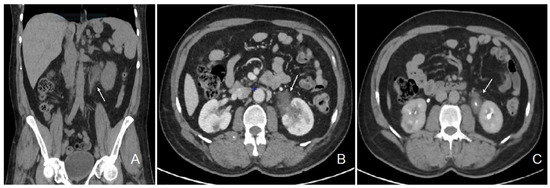

| Kidney involvement | Rarely described. Tubulointerstitial nephritis (rarely granulomatous), nephrocalcinosis and lithiasis | 2 to 10%: mainly nephrocalcinosis, renal stones. Granulomatous TIN in 20% (rarely alone) |

- Widdershoven, C.V.; Aarts, B.M.; Zondervan, P.J.; Henderickx, M.M.; Klompenhouwer, E.G.; van Delden, O.M.; Prevoo, W.; Montauban van Swijndregt, A.D.; van Moorselaar, R.J.; Bex, A.; et al. Renal biopsies performed before versus during ablation of T1 renal tumors: Implications for prevention of overtreatment and follow-up. Abdom. Radiol. 2021, 46, 373–379. [Google Scholar] [CrossRef] [PubMed]